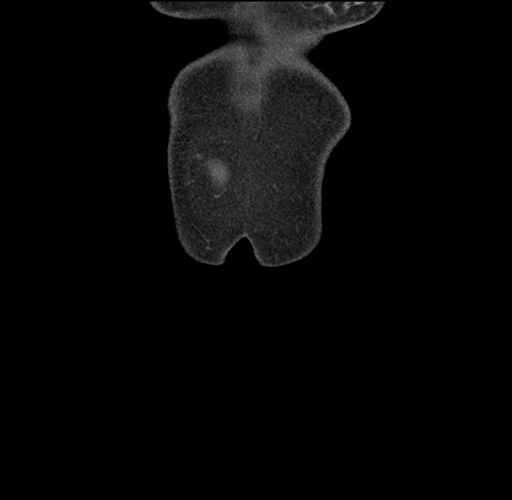

Imaging Analysis

Look through the patient's CT scan to identify any areas of concern for the necessary procedure.

Based on your CT findings, which issue(s) would give reason for "planned slowing down moment(s)" in this case?

Considering a standard left lateral sectionectomy procedure, what step(s) of the operation would you do differently in this case ?